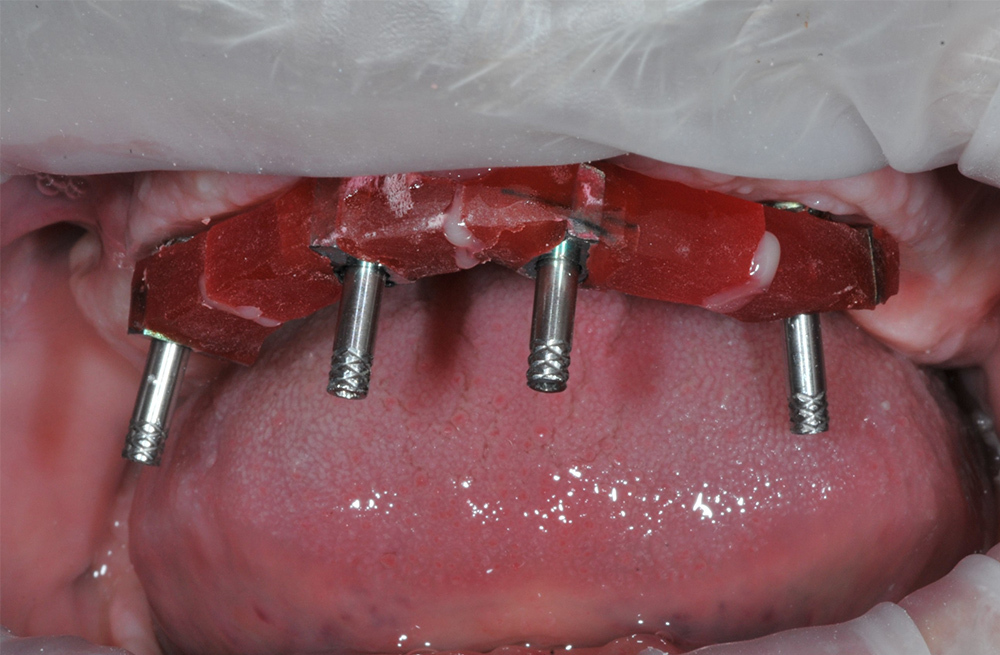

Тотальная реабилитация пациента с ятрогенными поражениями корней по схеме 6 на 6 и надёжной балочной конструкции